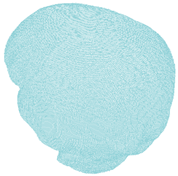

| Pia mater | LLC Elemance—GHBMC Model 2014; M. Ratajczak et al., 2019 [32,34] | 1.13 × 10−9 | 31.5 | ν = 0.45000 | shell 245,632 |  |

| Dura mater | LLC Elemance—GHBMC Model 2014; M. Ratajczak et al., 2019 [32,34] | 1.13 × 10−9 | 31.5 | ν = 0.45000 | shell 92,152 |  |

| Falx cerebri | LLC Elemance—GHBMC Model 2014; M. Ratajczak et al., 2019 [32,34] | 1.13 × 10−9 | 31.5 | ν = 0.45000 | shell 1197 |  |

| Tentorium cerebelli | LLC Elemance—GHBMC Model 2014; M. Ratajczak et al., 2019 [32,34] | 1.13 × 10−9 | 31.5 | ν = 0.45000 | shell 1669 |  |

| Superior sagittal sinus and transversal sinus | LLC Elemance—GHBMC Model 2014; M. Ratajczak et al., 2019 [32,34] | 1.04 × 10−9 | 28.2 | ν = 0.45000 | shell 10,627 |  |

| Bridging veins | Monea et al., 2014 [31] | 1.13 × 10−9 | 30 | 0.48000 | shell 10,627 |  |